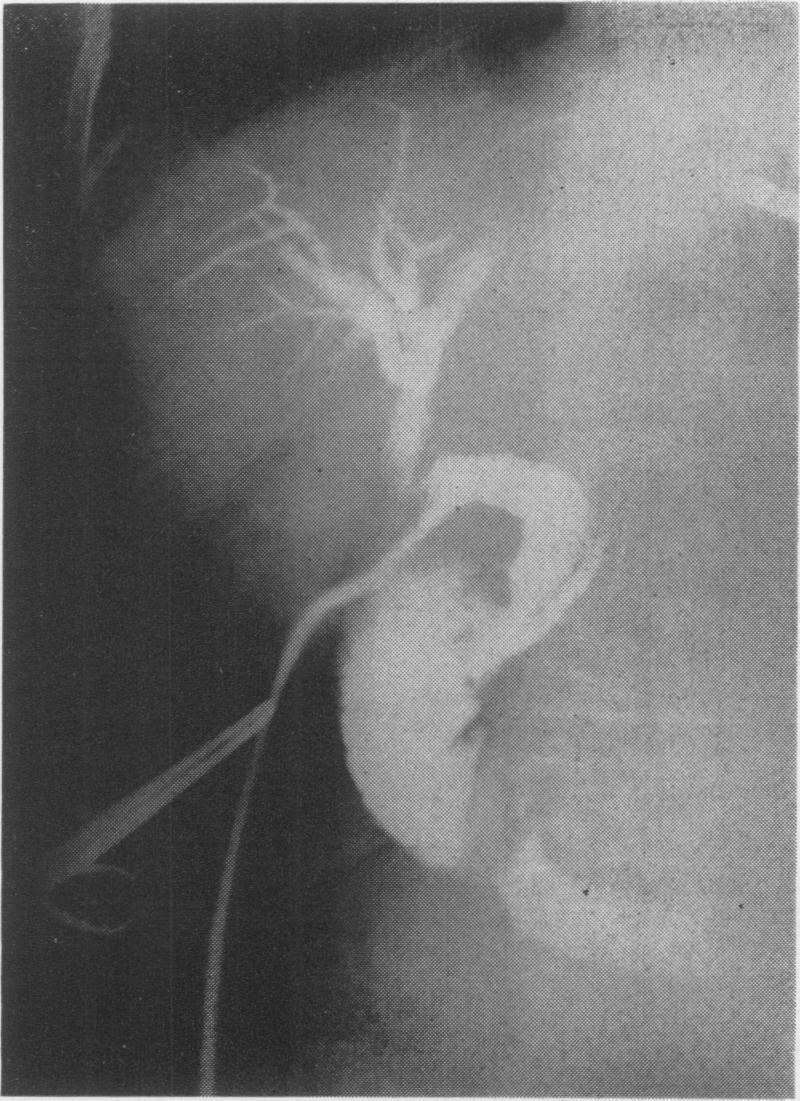

Residual common duct calculi.

Ann Surg. 1956 May;143(5):619-26; discussion, 626-7. doi: 10.1097/00000658-195605000-00008.